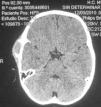

En el presente trabajo se presenta el caso de un varón de 4 años con fascitis en tejido celular subcutáneo craneal con erosión de la tabla externa y reacción perióstica circundante, respetando las meninges. El objetivo de este trabajo es destacar la ausencia de necesidad de tratamiento adyuvante con radioterapia o quimioterapia. Se lleva a cabo, además, una revisión de la literatura.

We present the clinical, radiological and pathological findings in a 4-year-old boy with cranial fasciitis in the deep, subcutaneous, soft tissue, with erosion of the outer table of the cranium, which also produced periosteal reaction, while respecting the inner table and meninges. The objective of this article is to highlight the absence of radiotherapeutic or chemotherapeutic adjuvant treatment. In addition, an exhaustive review of the literature is also presented.